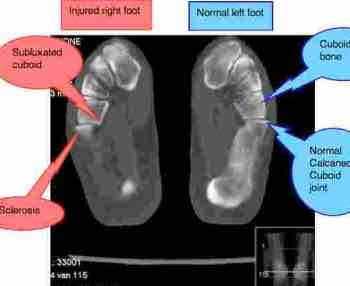

X-ray of feet